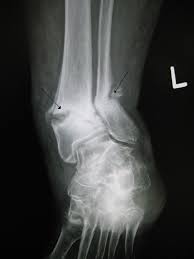

Unikátní vynález speciálního lepidla, které by mohlo značně usnadnit léčbu zlomenin kostí včetně tříštivých, si na své konto mohou připsat specialisté z výzkumného centra CEITEC a lékaři z Fakultní nemocnice Brno.

Testy lepidla na lepení zlomených kostí probíhaly v první fázi na kostech mrtvých zvířat a poté bylo lepidlo testováno i na kostech lidských.

Při praktickém využití lepidla v medicíně se počítá se zkrácením doby fixace a celkových zlepšením hojení zlomených kostí.

Lepidlo má schopnost slepit kost, není toxické a indukuje kostní růst. Proroste kost a pevně ji spojí.

Ztuhnutí lepidla a manipulační pevnost spoje nastává u většiny kostí do 120 sekund a k úplnému vytvrzení lepidla pak dochází během následujících 72 hodin.

Lepidlo na zlomené kosti má potenciál zkrátit léčbu tříštivých zlomenin několika týdnů na několik dní.

Lepidlo na zlomené kosti přitom musí splňovat řadu nároků, nesmí být toxické pro organismus a kostní tkáň, musí být vstřebatelné a také dostatečně porézní. Dále musí podporovat vrůst novotvořené kostní tkáně do lepidla i do fixovaného kostního úlomku.